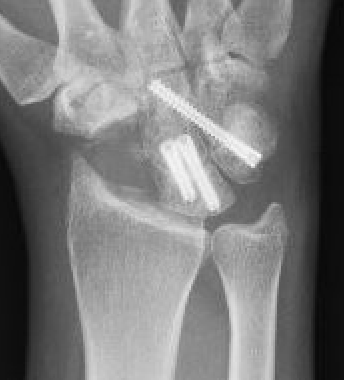

Fixation options

K wires

Headless compression screws

Dorsal locking plates

Staples